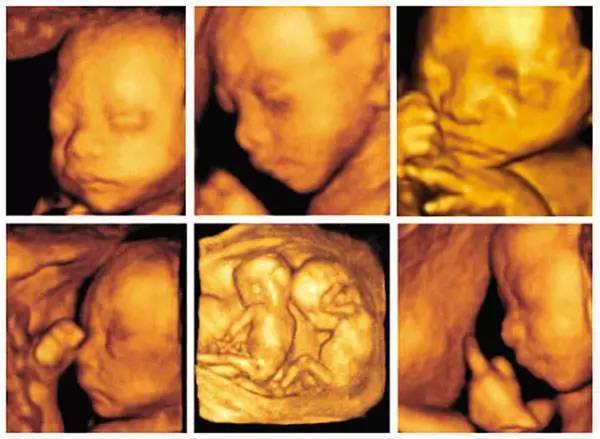

胎儿四维彩超最佳时间

六个月男胎儿四维彩超

胎儿6个月四维图片

胎儿四维彩超照 VS 出生后的照片 惊人相似

胎儿四维彩超图